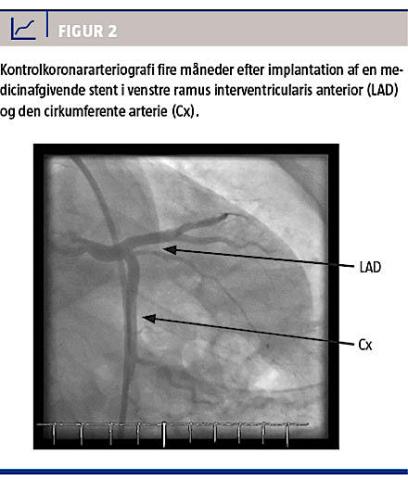

På grund af vedvarende smerter, til trods for kontinuerlig nitroglycerininfusion, og de parakliniske fund blev patienten overflyttet til et hjertecenter med henblik på subakut koronararteriografi (KAG), som ikke viste tegn på iskæmisk hjertesygdom, idet der var glatvæggede kar i alle segmenter uden påviselig ateromatose, men den gav mistanke om en dissektionsmembran helt proksimalt i venstre ramus interventricularis anterior (Figur 1). Ved en supplerende optisk koherenstomografi bekræftedes dissektion ved bifurkaturen mellem venstre ramus interventricularis anterior og den cirkumferente arterie samt med dissektionsmembraner ned i begge kar (Figur 1). Efter konference med thoraxkirurger blev der lagt en medicinafgivende stent (Taxus 4,5/16 mm) i hvert kar op mod hovedstammen med godt angiografisk resultat. Patienten blev tilbageflyttet til stamsygehuset og udskrevet efter et par dages observation og dobbelt blodpladehæmmende behandling.